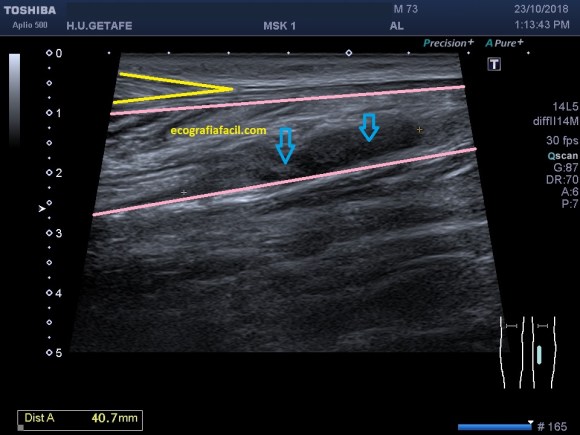

Una vez que hemos encontrado la lesión, es momento de estudiarla detenidamente, su aspecto, tamaño bordes y vascularización son vitales para que la radióloga pueda efectuar un informe.

La imagen 3 y 4 son parte estudian en eje largo y corto las medidas de la lesión en los tres ejes del espacio, en ocasiones, podemos tener más de una lesión. Siempre super atentos si las lesiones son intra o extratesticulares.